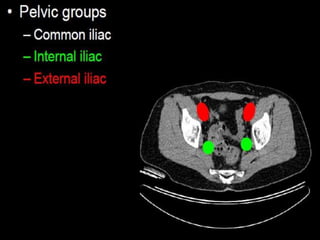

CT cross sectional anatomy.